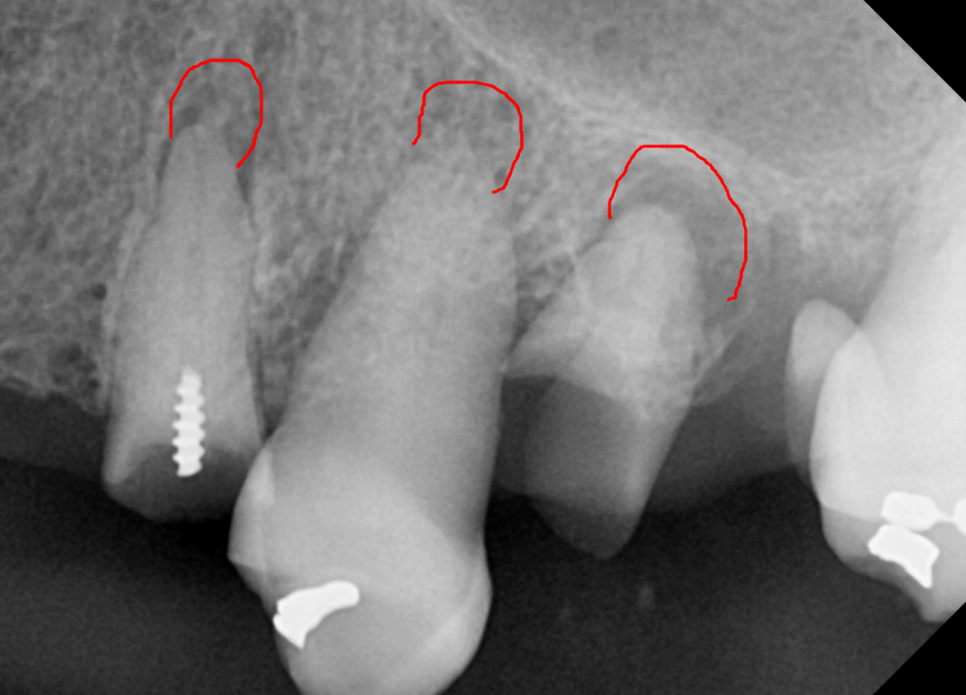

파노라마와 CT를 통해 살펴보니

뿌리 끝에 염증이 가득 잡혀 있었죠.

가장 튼튼해서 살려 쓸 수 있는

위쪽 치아 2개(#14, 27)만 남기고

나머지는 안타깝게도 발치를 결정했습니다.

아래쪽 앞니들은 잇몸뼈가 많이 녹아 흔들리고 있어

총 4개의 치아를 발치하기로 했습니다.

상악: 임플란트 8개 식립

상악동 거상술 및 뼈이식